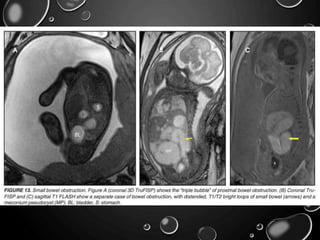

SMALL BOWEL ATRESIA

• DUE TO THE DISRUPTION OF THE MESENTERIC BLOOD SUPPLY TO THE

AFFECTED SEGMENT OCCURRING AFTER THE 12TH GESTATIONAL

WEEK.

• ISCHEMIC NECROSIS LEADS TO DAMAGE OF THE INTESTINAL

SEGMENT, POSSIBLY LEADING TO FIBROUS SCARRING OR, IN ITS

EXTREME FORM, THE DISAPPEARANCE OF BOWEL.

• IN THE CASE OF THE JEJUNUM, ATRESIAS TEND TO BE MULTIPLE. THE

JEJUNUM HAS THE CAPACITY TO DILATE CONSIDERABLY BEFORE

PERFORATION OCCURS. THIS IS IN CONTRADISTINCTION WITH ILEAL

ATRESIAS, WHICH TEND TO BE SOLITARY, AND WHERE PERFORATION

MAY OCCUR WITH VERY LITTLE DILATATION.

• FETAL ASCITES IN THE SETTING OF BOWEL OBSTRUCTION SUGGESTS

BOWEL PERFORATION